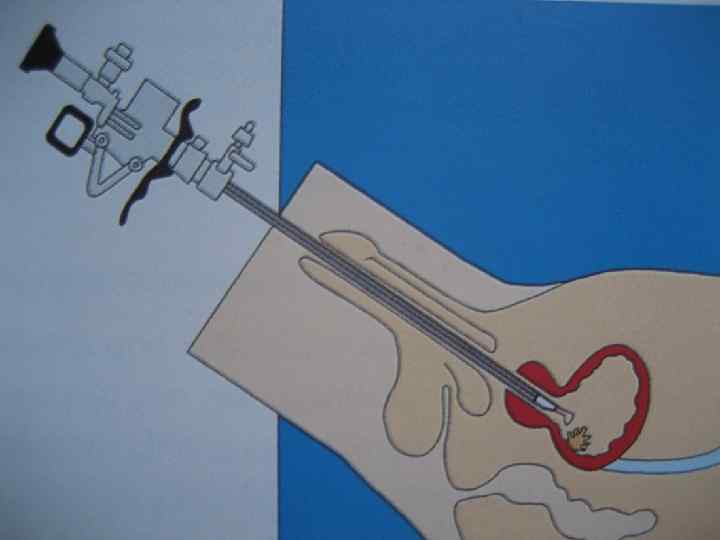

Опухоль м/п Recomendations • Physical examination (including digital rectal and pelvic examination) • Renal and bladder ultrasonography and/or IVP • Cystoscopy with description of the tumour: size, site, appearance (a diagram of the bladder should be included) • Urinalysis • Urinary cytology • TUR with: • biopsy of the underlying tissue • random biopsies in the presence of positive cytology, large or non-papillary tumour • biopsy of the prostatic urethra in cases of Tis or suspicion of it 24

Опухоль м/п Лечение • После установления диагноза необходимо определить стадию заболевания- поверхностная опухоль (Ta-T 1), CIS или инвазивная опухоль (more than T 1). Потому что лечение и наблюдение при этих трех стадия отличается. 26

Bladder cancer Treatment • • Ta-T 1 are superficial bladder tumours. Treatment will be directed towards the prevention of recurrence and progression. Tis is a potentially highly malignant disease that can still be treated, with bladder instillations of bacillus Calmette. Guerin (BCG). A cystectomy is necessary when this fails to cure the disease after two cycles of 6 -8 weekly instillations. Tumours of T 2 or higher category are infiltrating tumours and cystectomy will be necessary in the majority of cases. Bladder preservation can be an option in selected cases. N+ and metastatic disease require additional therapeutic approaches. 27

Bladder cancer Treatment of Ta-T 1 lesions • Prognostic factors: Number of tumours Recurrence rate in the previous period Size of the tumour • One single chemotherapeutic instillation immediately after TUR by epirubicin or mitomycin • A 4 -8 week course followed by monthly instillation with chemotherapeutic agents in intermediate- and high-risk tumours • Chemotherapeutic agents used for bladder instillations 28